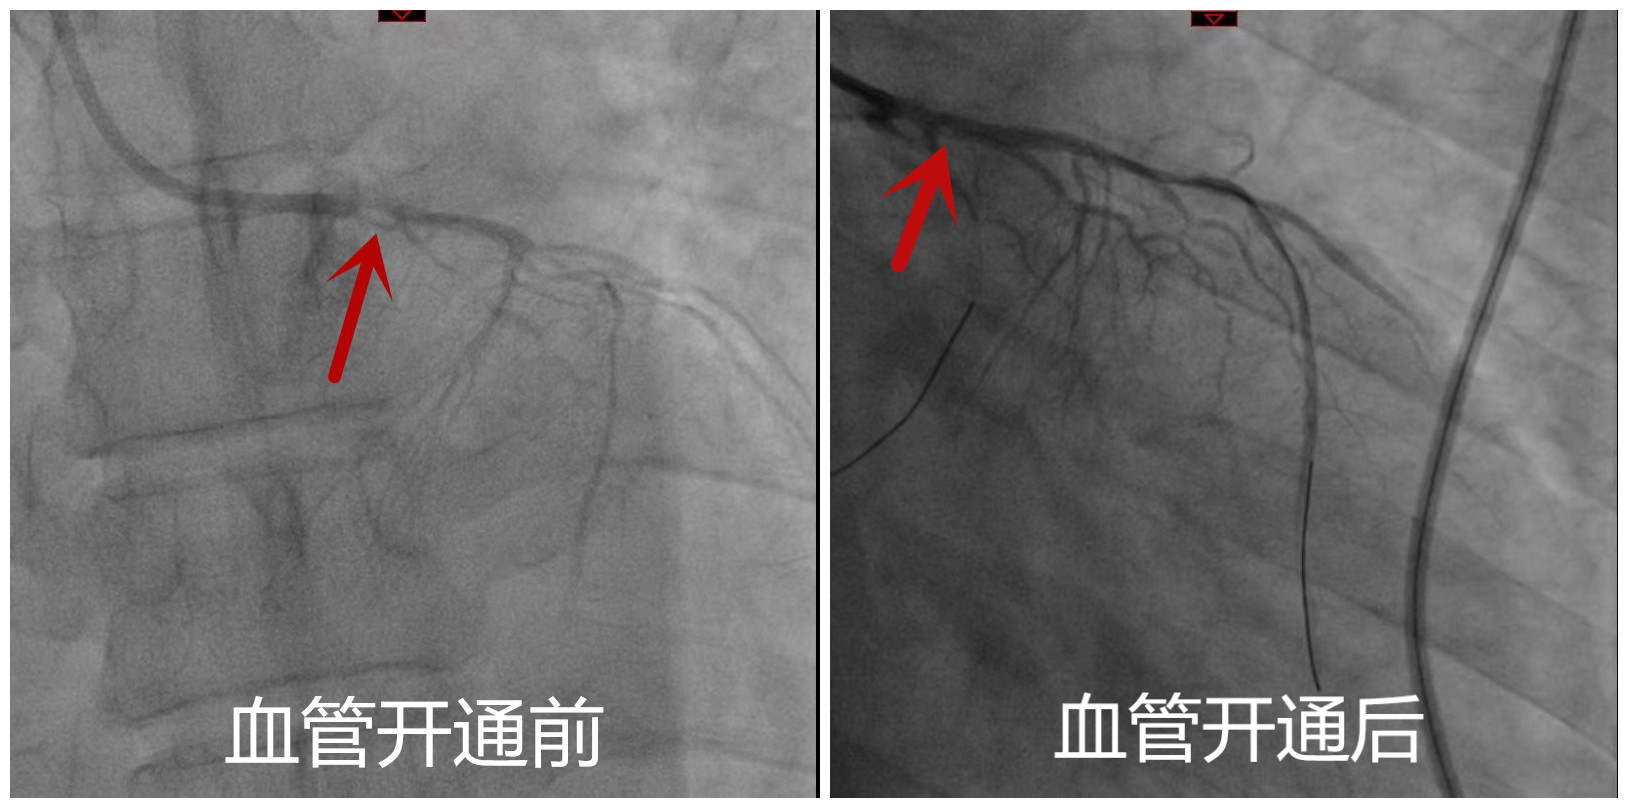

16时21分 股动脉穿刺成功,迅速送入介入导管并进行造影,确诊左主干次全闭塞、前降支闭塞、回旋支次全闭塞;

16时25分 两根导丝分别通过闭塞血管进入前降支及回旋支远段;

16时30分 成功行前降支、回旋支、左主干闭塞及次全闭塞处血管内球囊扩张,患者冠脉血流恢复。下意识地我们看了一下墙上的时钟,从开始穿刺,到恢复血流我们仅用了10分钟。这是挽救生命的10分钟;